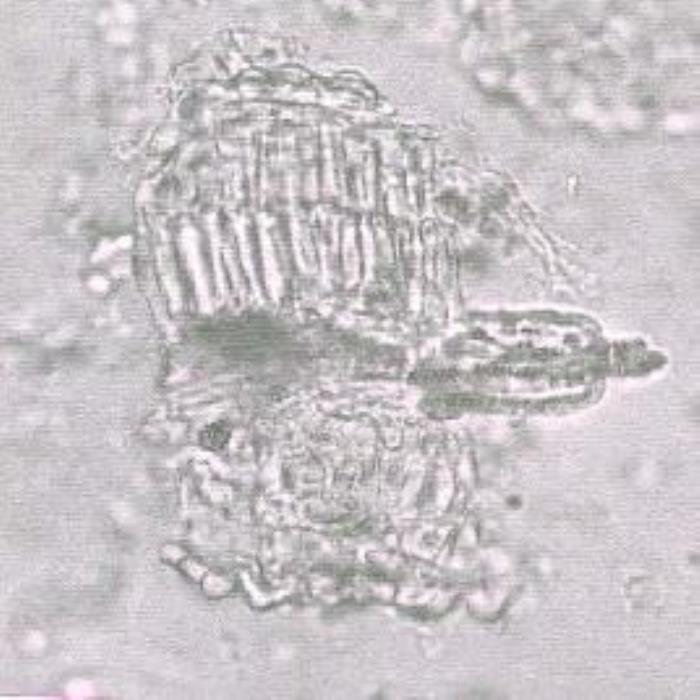

الورقة: المقطع العرضي للورقة یبین أن النسيج العمادي بھا موجود تحت طبقة بشرة واحدة فقط. طبقة البشرة العلیا تتكون من خلایا حليمية تغطیھا أدمة سميكة مخططة تخطيطا طفيفا. النسيج العمادي یتكون من طبقتين من الخلايا المستطيلة المتراصة بصورة لصيقة وهي تتميز بالجدر المستقيمة السميكة كما تحتوي على بعض الجزئيات الملونة. خلايا النسيج الوسطي الإسفنجي متطاولة وبعض هذه الخلايا تحتوي على بلورات عنقودية وحيدة من أكسلات الكالسيوم في كل خلية. والنسيج الإسفنجي يضم أيضا غددا كبيرة الحجم وتخترقه أيضا انسجة وعائية ذات زوايا تضم اوعية بها ترسبات لولبية وشبكية. طبقة البشرة السفلي تتكون من خلايا بيضاوية او مدورة صغيرة الحجم تغطيها ادمة سميكة مرتفعة قليلا عن سطح الورقة ولكن هذه الخلايا غير حليمية الشكل. وطبقة البشرة السفلي تضم ثغرات مدورة الشكل تقريبا وهي من النوعية متباينة الخلايا وتتوزع على البشرة بصورة معقولة.

الساق: مسحوق الساق يبين وجود الياف طويلة بها ترسبات لجنينية وهذه الالياف متراصة بصورة لصيقة وهي ذات جدر سميكة والجزء الداخلي من خلايا متسع. وتتواجد أيضا مجموعات كبيرة من الاسنجة الوعائية المتراصة بصورة لصيقة وهي تضم أوعية بها ترسبات شبكية ولوبية. (DPS ZCHRTM Unpub. Results)

- (أ) قطعة صغيرة من الورقة تبین خلايا البشرة العلیا الحليمية.

- (ب) مقطع عرضي لجزء من الورقة یبین طبقتين من النسيج العمادي، خلايا النسيج الاسفنجي (بعض هذه الخلايا يحتوي على بلورات عنقودية من أكسلات الكالسيوم)، الأنسجة الوعائية التي يحتويها النسيج الإسفنجي، خلايا البشرة السفلي المستديرة أو البيضاوية.

- (ج) قطعة صغيرة من الساق تبين الالياف الطويلة المتراصة بشكل لصيق وبتبين ان جدر خلاياها سميكة بينما بواطن الخلايا واسعة وهذه الألياف تحيط بمجموعة من الانسجة الوعائية التي تضم اوعية بها ترسبات شبيكة ولوبية. (الصور كلها مكبرة 250 مرة).